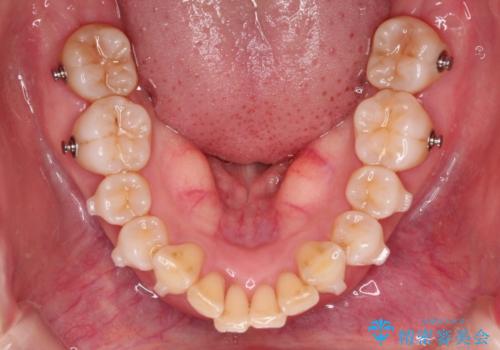

- 前歯が出ていることを主訴に来院されました。

インビザラインにて臼歯部の遠心移動及びIPRを行なっています。

叢生量が多いケースでしたが、綺麗な歯並びとなり患者様にも満足していただきました。